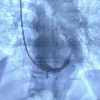

“Abbiamo eseguito questo intervento invasivo ma non chirurgico – ha spiegato Bonfantino - in un paziente di 63 anni, in anestesia locale, che è consistito nell’impianto di uno stent metallico (reducer), a forma di clessidra,  attraverso la vena giugulare, all’interno del seno coronarico, cioè la vena che sbocca nell’atrio destro del cuore e che drena tutto il sangue venoso di origine cardiaca, per poi raggiungere i polmoni ed essere ossigenato.  Questa procedura  - ha aggiunto -trova indicazione in quei pazienti coronaropatici sintomatici, che lamentano angina pectoris nonostante terapie farmacologiche ad alto dosaggio.  La presenza di tale sintomatologia, anche assumendo una terapia farmacologica ottimizzata, determina un aumentato rischio ischemico cardiaco e genera grande frustrazione per i pazienti che non sono quindi in grado di svolgere in serenità le normali attività quotidiane”.

L’impianto dello stent reducer in sala è stato coordinato dal dottor Maurizio Turturo, responsabile della UOS Emodinamica, e dal dottor Francesco Cassano. “Grazie alla particolare morfologia dello stent, a forma di clessidra – ha detto Turturo - si determina un rallentamento del drenaggio venoso cardiaco, permettendo la persistenza nel cuore di sangue ancora ossigenato e quindi il rilascio di una maggiore quantità di ossigeno al muscolo cardiaco. Ciò determina, in un’alta percentuale di casi, la risoluzione dei sintomi anginosi del paziente e il sensibile miglioramento della qualità di vita del paziente”.